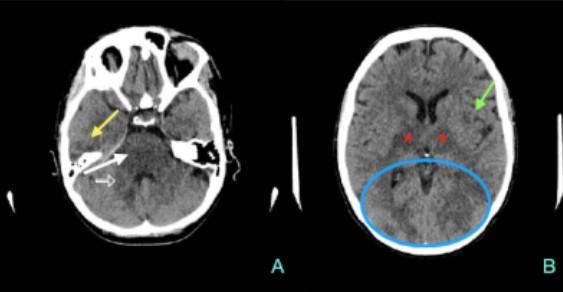

Resonancia magnética: secuencias ponderadas en T1 con gadolinio en plano axial (A), sagital (B) y coronal (C): Masa extraaxial de aspecto heterogéneo, bien definida, con un intenso realce periférico, de 42 x 41 x 38 mm (AP x TR x CC) en la línea media frontobasal. La lesión está en contacto con la lámina cribiforme y parece originarse del bulbo y tracto olfatorio izquierdo. Aisladas formaciones quísticas periféricas. Secuencia ponderada en T2 plano coronal (D): extensa área de hiperseñal T2 que se extiende por la sustancia blanca del lóbulo frontal izquierdo.